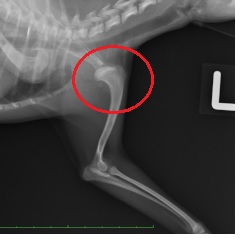

整復前 整復後

高所からの転落により左肩関節を脱臼。鎮静下にて整復→外固定を約2週間実施。